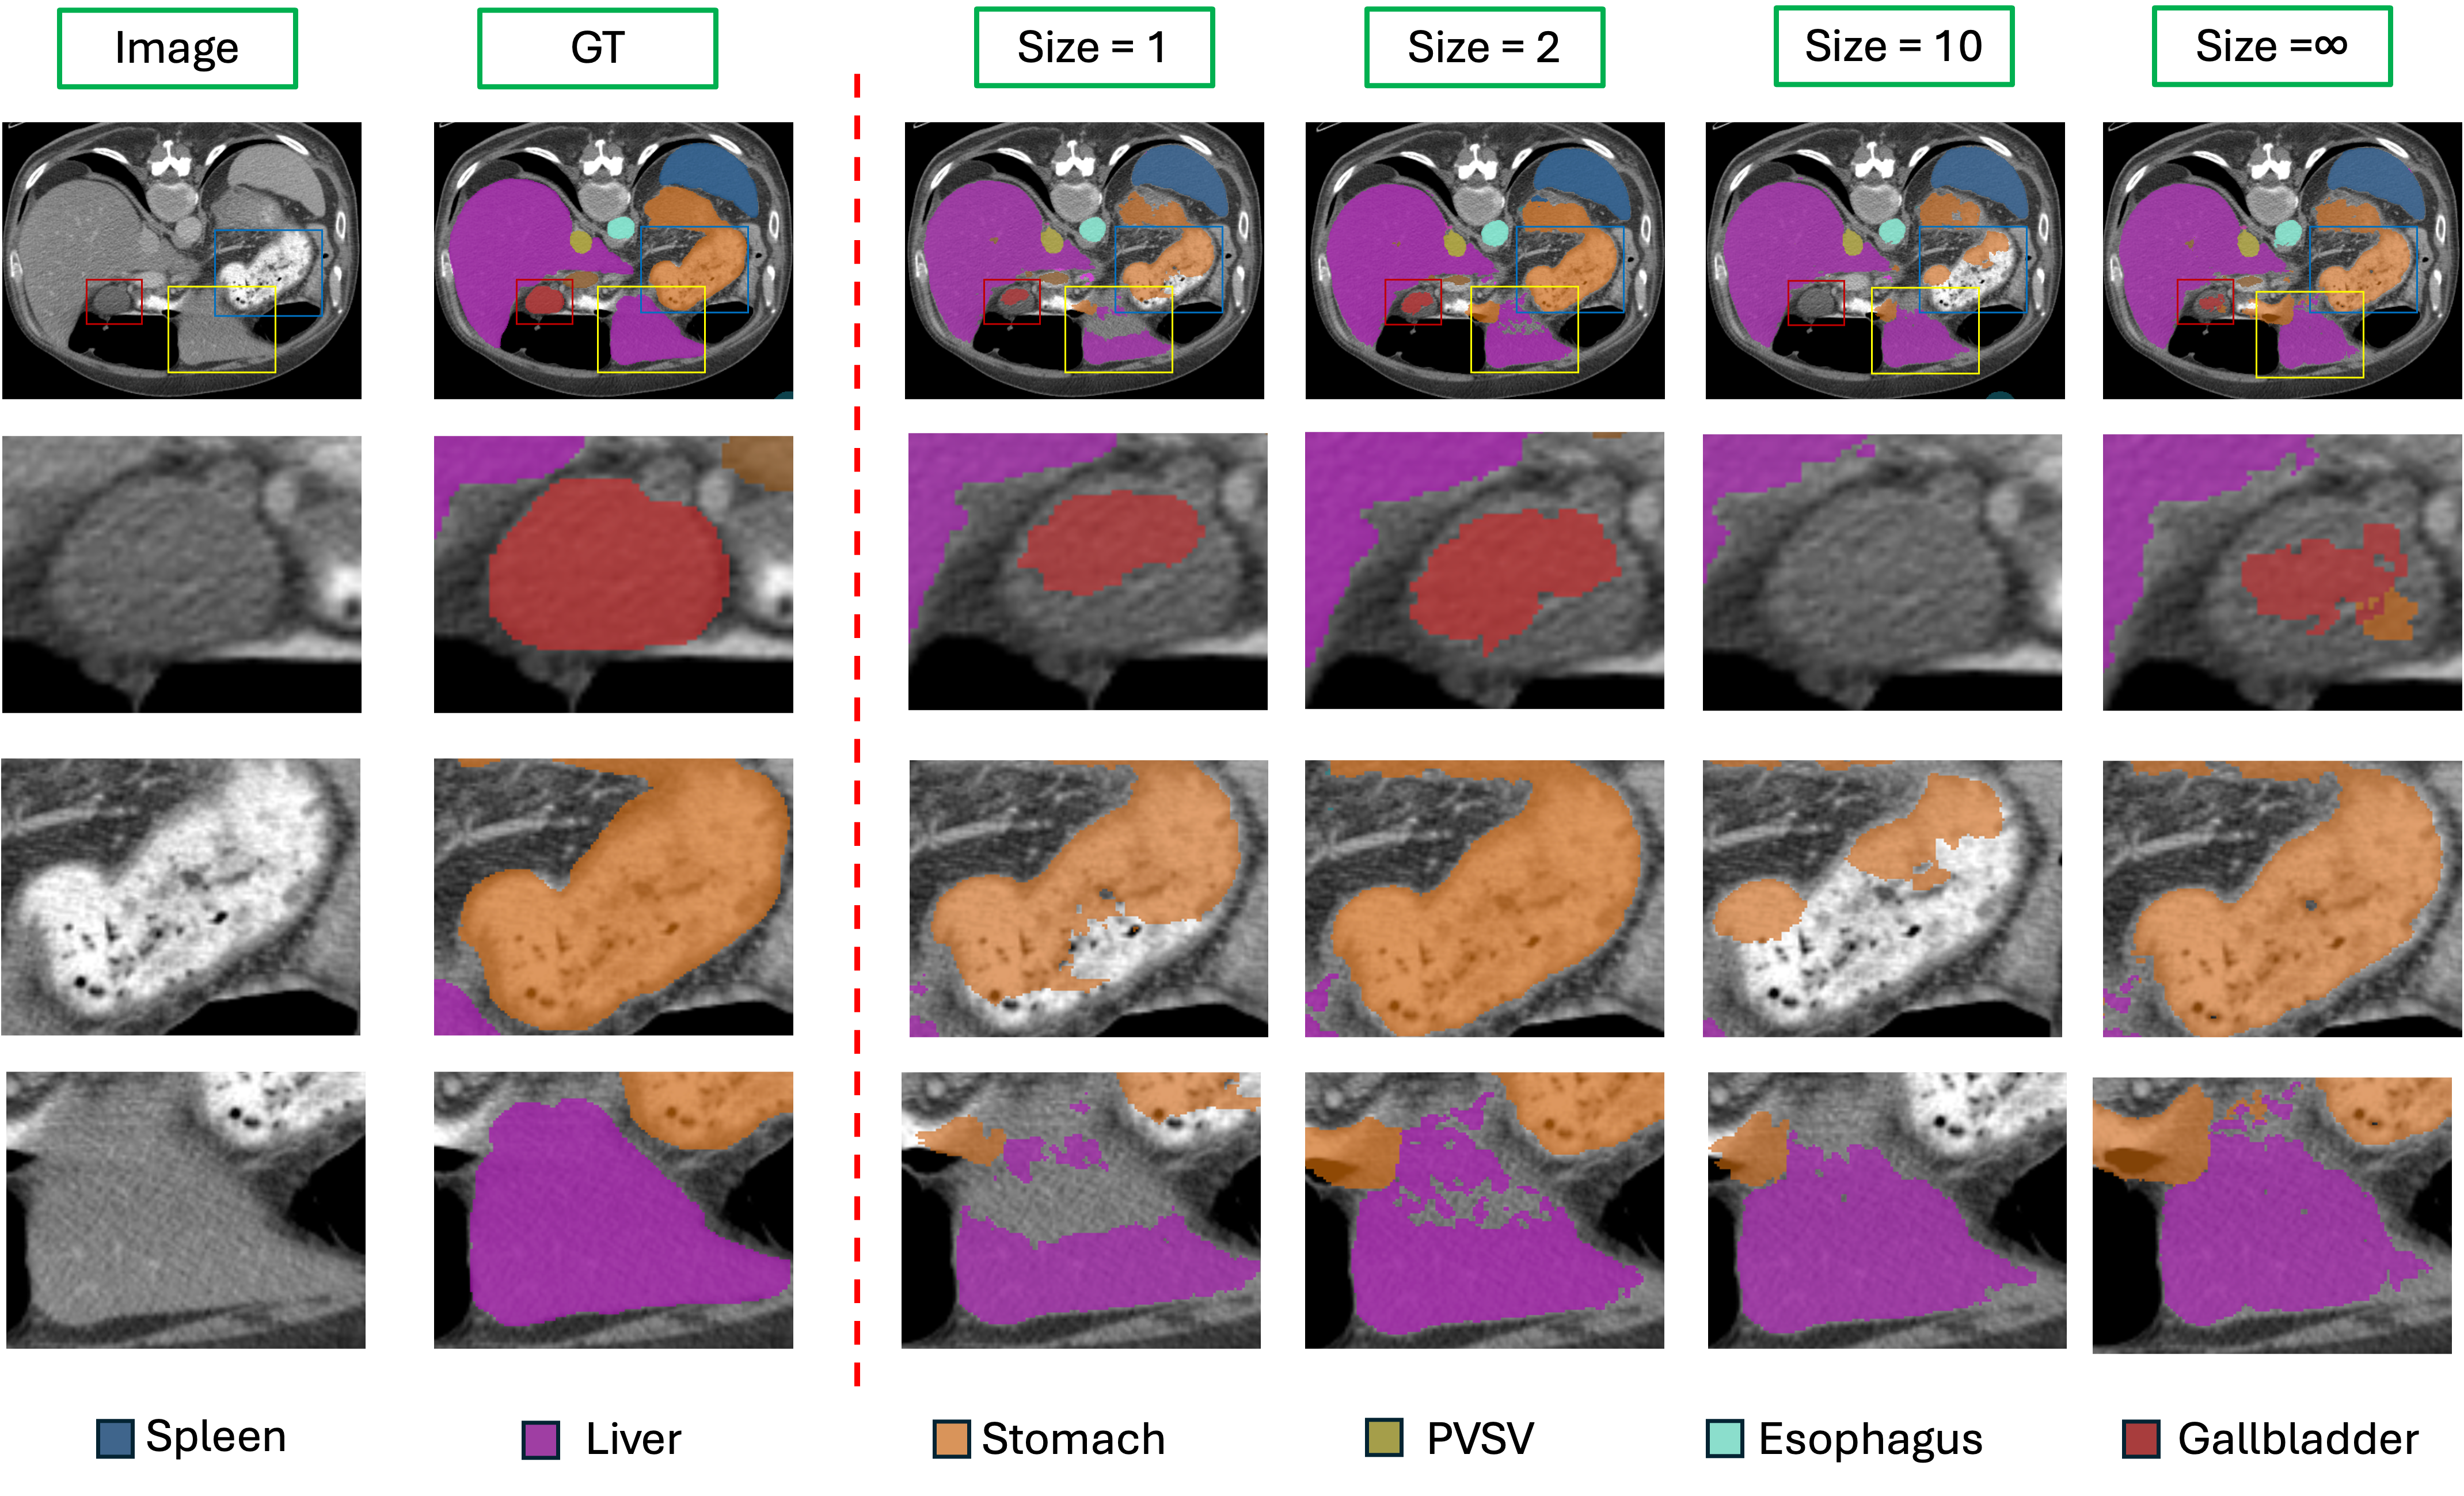

Figure 8: Effects of DTC with different receptive fields on the UNETR model. The first row shows a 2D slice of the 3D CT segmentation results. The second, third, and fourth rows display zoomed-in views of the regions highlighted by red, blue, and yellow rectangles, respectively. PVSV stands for Portal Vein and Splenic Vein.

We tested the impact of receptive field size on model performance using the 2D ISIC dataset and the 3D BTCV dataset, evaluating both linear interpolation and transposed convolution models. Results, shown in Table 5, indicate that the DTC method is particularly sensitive to receptive field size. When the receptive field exceeds 10, model performance declines notably. While UNETR achieves high DICE scores with a full receptive field, it exhibits low NSD performance, suggesting that an overly large receptive field may reduce the model’s precision in capturing segmentation boundaries. Therefore, a smaller receptive field may improve boundary detection, but the default receptive field of 2 is not always optimal. Fine-tuning this receptive field yields better results. On the other hand, we performed a visualization analysis (Fig. 8) of the results for the UNETR model. We observed that adjusting the receptive field can improve overall model performance. However, in multi-class segmentation tasks, DTC does not consistently yield significant improvements for every organ and may result in lower segmentation performance for individual organs. For example, as shown in the (Fig. 8, segmentation of the stomach and gallbladder is clearly improved at the optimal receptive field, whereas the liver’s performance deteriorates compared to using a receptive field of 10 or the full image. These observations suggest that the effectiveness of DTC may vary across organs in multi-class scenarios, highlighting the importance of organ-specific considerations when applying advanced upsampling techniques.